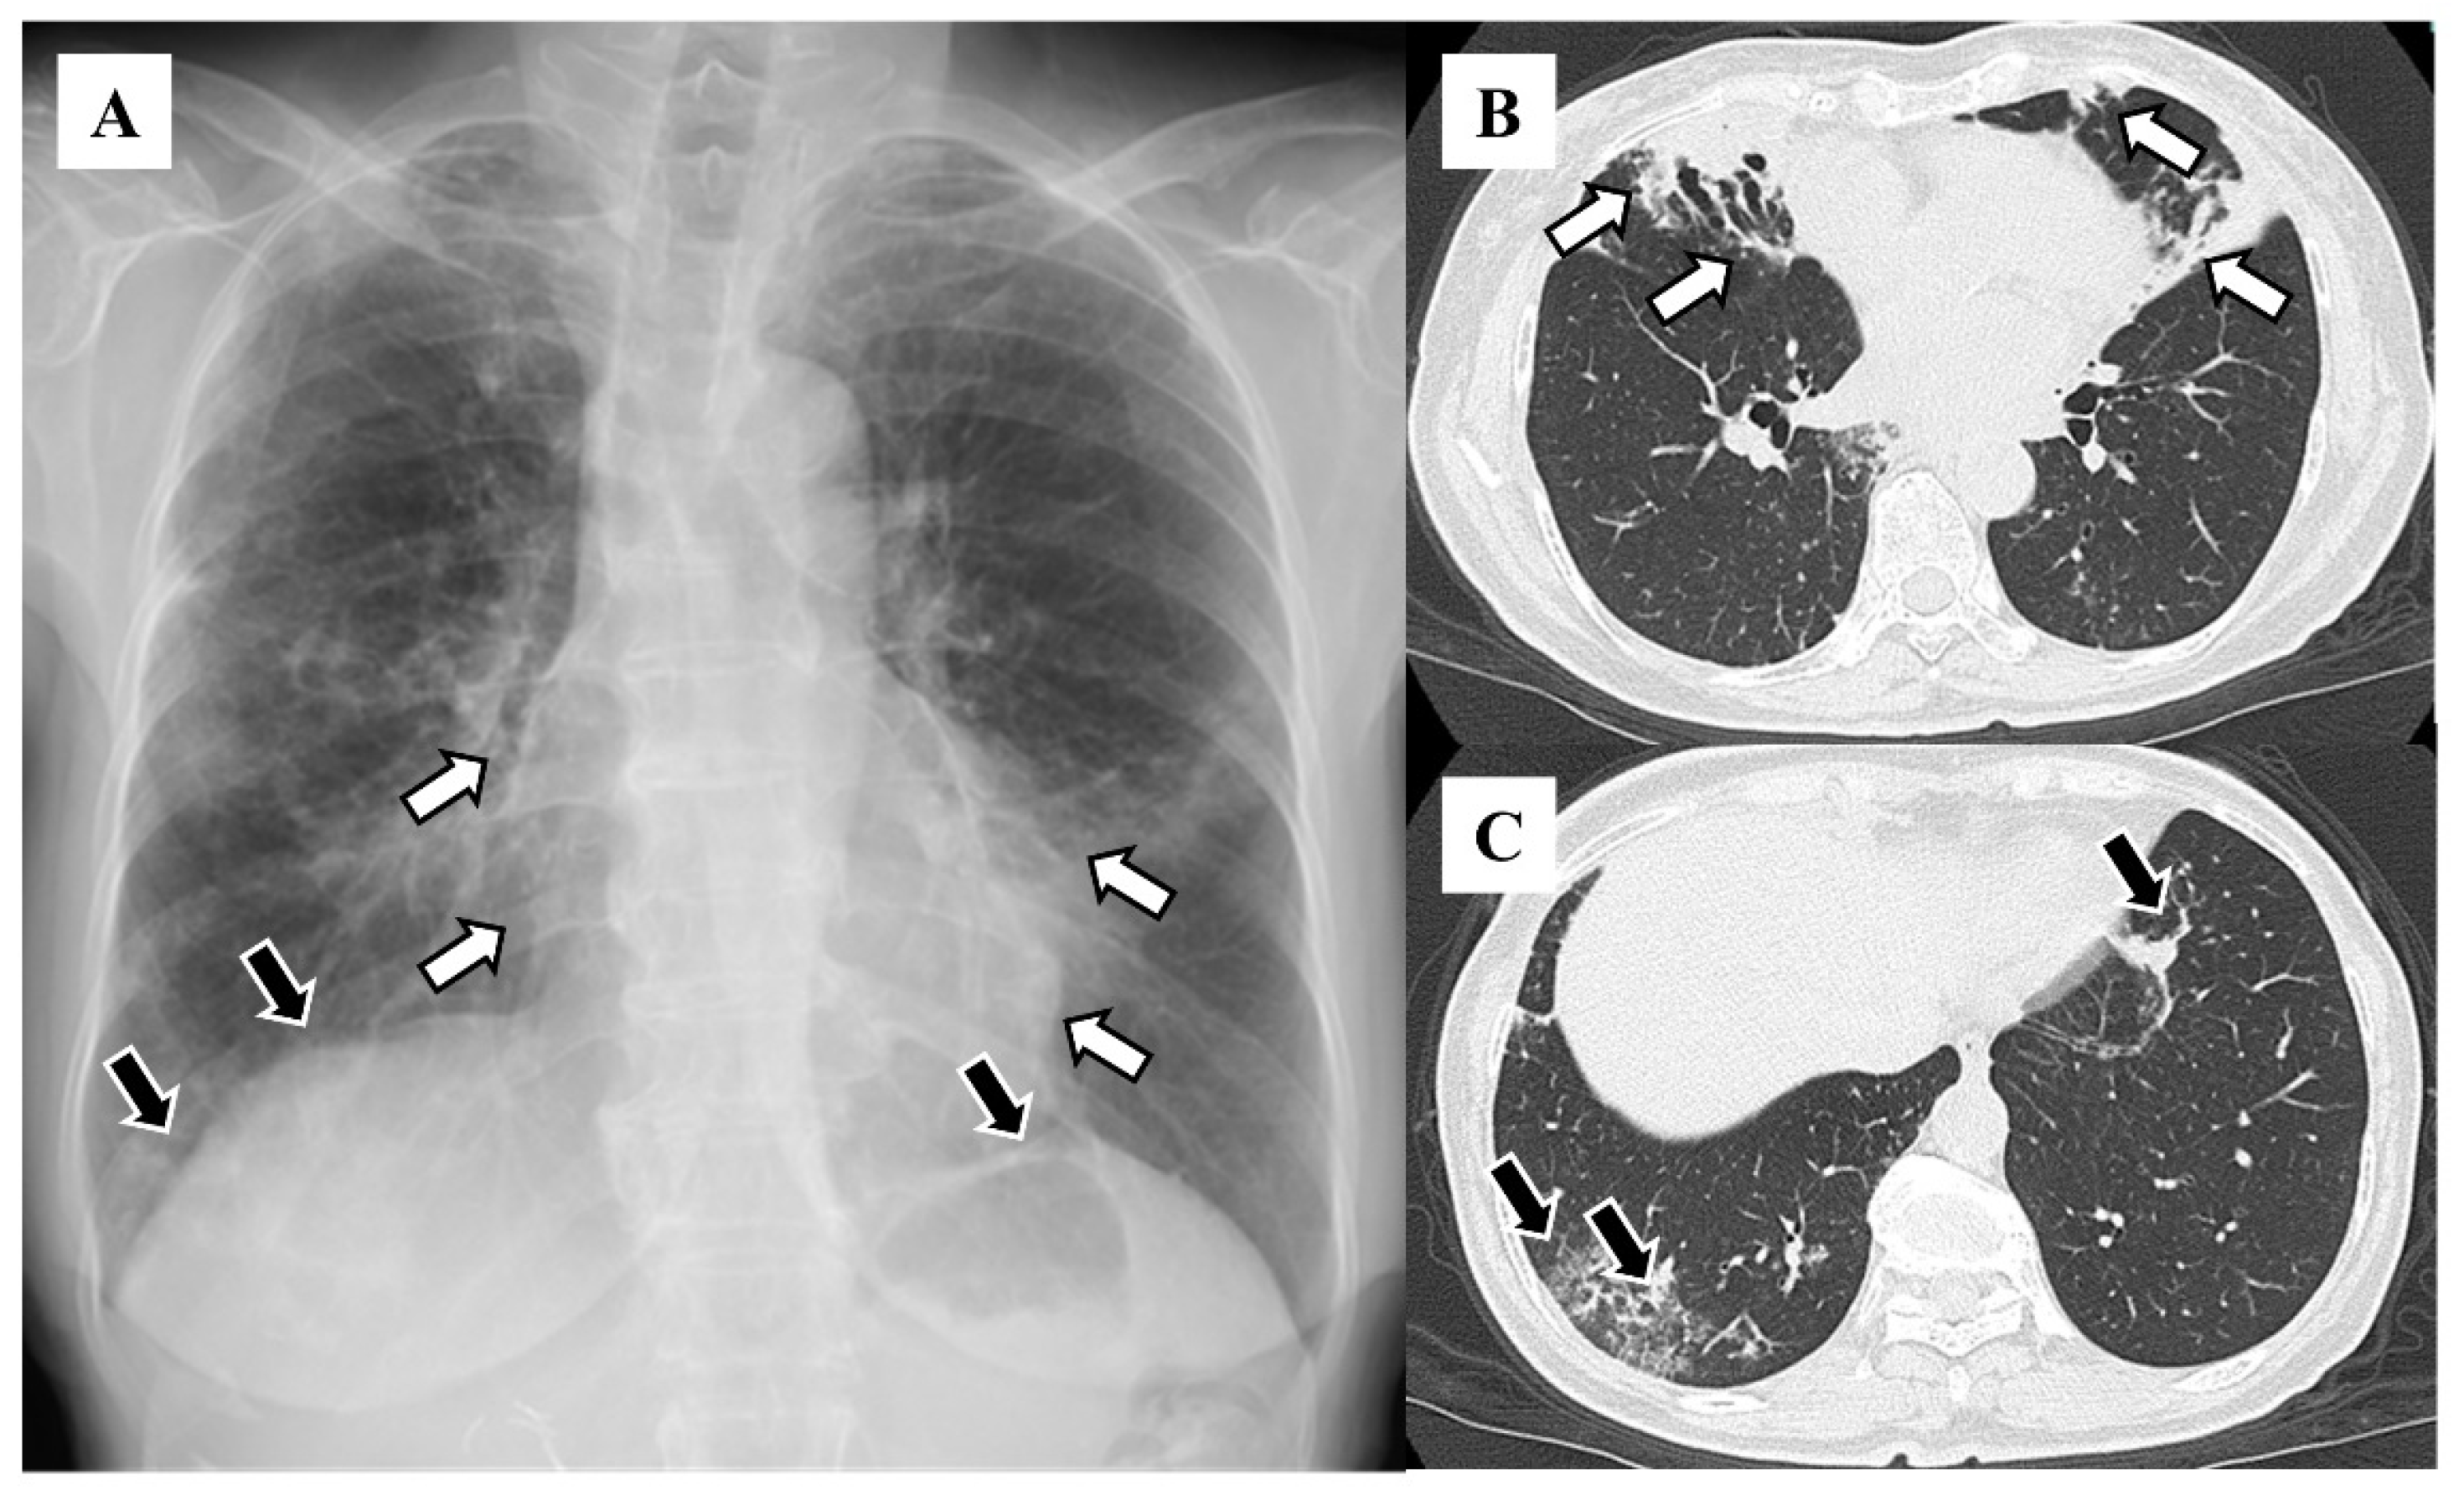

| Granular shadows | 115 (88.5) |

| Vague cardiac silhouette | 63 (48.5) |

| Nodular shadows | 59 (45.4) |